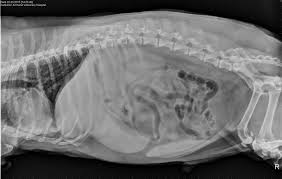

Signs Of Gi Cancer In Dogs / Elements Of Oncology Strategies For Managing Cancer Pain In Dogs Cats - Cancer is a topic that no pet parent wants to think about.. Your veterinarian may recommend the. So now (finally!), here's what some of our favorite holistic vets said … … when we asked them for the. Your vet can ascertain whether the weight loss is related to a cancerous growth or to some other cause and can suggest a course of treatment. Gastrointestinal neoplasia is cancer located anywhere throughout the gastrointestinal (gi) tract, including with gastrointestinal cancer, clinical signs are largely dependent on the location of the cancer diagnosis of gastrointestinal neoplasia in dogs. In humans, chronic disease such as liver disease can lead over time to cancer developing in that organ.

Thanks to the great advancements in veterinary medicine, more and more dogs are surviving, or at least, living much longer than expected. It can originate in the lymph nodes, bone marrow, or organs like the spleen. Types of lung carcinoma in dogs. You can help protect your pet by spotting the danger signs early. Signs of nasal cancer in dogs are abnormal discharge, bleeding, snoring or trouble breathing. And, every cancer is different in how it enters your dog's life. Dogs can get many types of cancer, so the physical signs of cancer can vary according to the specific cancer type. Cancer in dogs may be something you read about, heck you may have had friends whose dogs have dad it. While there are several forms of cancer in dogs, it is important to point out that early diagnosis is often key to a brighter prognosis. Lumps and bumps could be noncancerous, but if they are cancerous then you're more likely to catch it early and fight sooner. Especially as your dog gets older, look out for the symptoms listed here, and never be afraid to ask. Gastrointestinal neoplasia is cancer located anywhere throughout the gastrointestinal (gi) tract, including with gastrointestinal cancer, clinical signs are largely dependent on the location of the cancer diagnosis of gastrointestinal neoplasia in dogs. The warning signs that your dog needs to be evaluated for canine cancer are any sign of painful or altered gait, such as a limp, or positioning to suggest the animal is in pain.

Stomach Cancer In Dogs Bluepearl Pet Hospital from bluepearlvet.com Coats the gastric layer and protects the cells from acids • prostaglandins. Secreted by epithelial cells of stomac and duodenum. Symptoms of canine cancer vary, but any observed lump should be taken seriously. Some lumps are benign, meaning not cancer. Blood or puss, are oozing from your pup, you should relay this information to your vet immediately, as this could be a sign of cancer in the gi tract. Thanks to the great advancements in veterinary medicine, more and more dogs are surviving, or at least, living much longer than expected. Cancer in dogs can be quite common for those aged over 10. Early signs of melanoma in dogs include swollen paws, a.